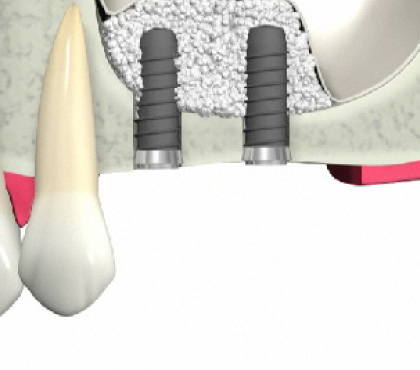

歯槽骨が吸収し、上顎洞が下がっています。このままではインプラントが突き抜けてしまうためインプラントはできません。

上顎洞が上に押し上げられ、インプラントを埋入するスペースができました。骨の材料も充填されているのでインプラントは安定します。

ソケットリフト方法

インプラントを埋入します。

骨が少ない場合②

インプラントを支えるための歯槽骨が十分でないためインプラントはできません。

インプラントを支えるための歯槽骨が作られました。インプラントを埋入する事が出来ます。

GBR法